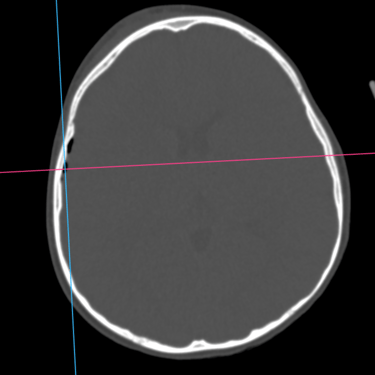

La fractura craneal es una lesión que puede producirse tras un traumatismo craneoencefálico, con riesgo de comprometer el cerebro y las estructuras intracraneales. Los síntomas incluyen dolor local, edema, hematomas y, en casos graves, alteración del nivel de conciencia. La tomografía computarizada (TC) es el estudio de elección para su diagnóstico, ya que permite identificar con precisión el trazo de fractura, desplazamientos óseos, hemorragias asociadas y la afectación de senos venosos o base de cráneo. Un diagnóstico temprano mediante TC es esencial para definir la conducta terapéutica y prevenir complicaciones neurológicas potencialmente graves.